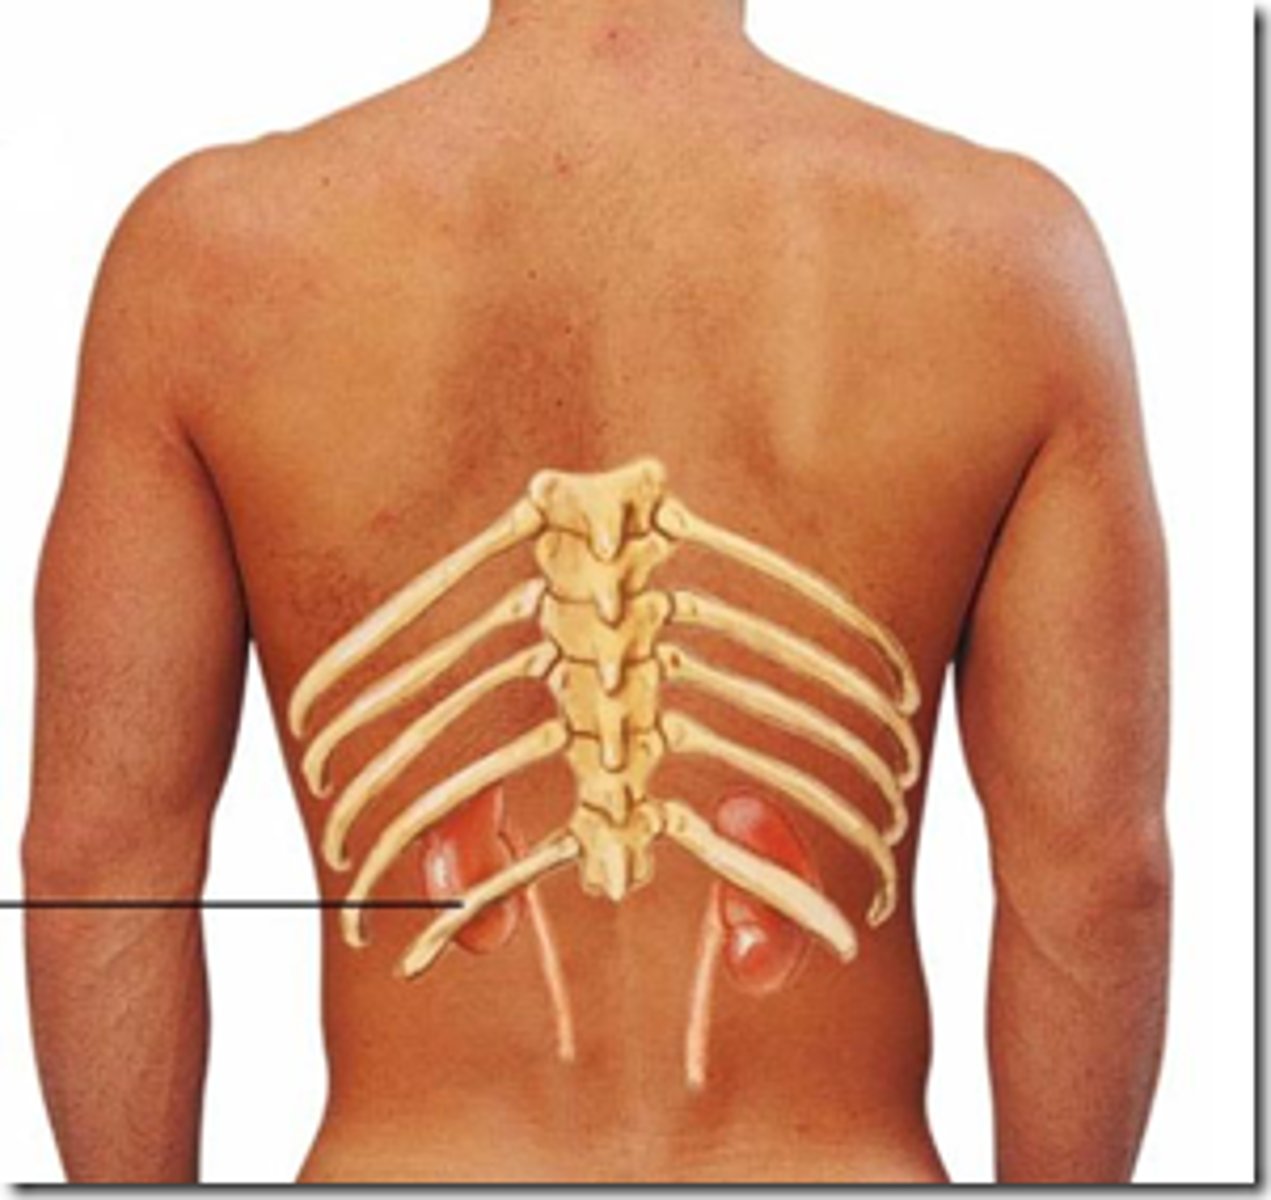

Why are the palpable dorsal spinous processes caudal to the middle of their corresponding bodies?

the processes project inferiorly

What is the suprasternal notch level to?

T2-T3

What is the sternal angle (manubriosternal joint) level to?

T4-T5

What is the xiphisternal joint level to?

T9